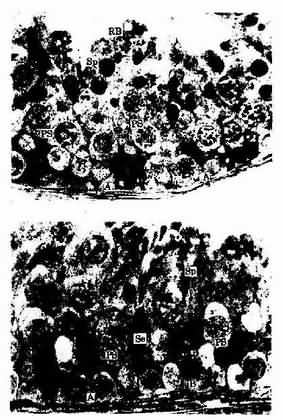

1.生精细胞包括精原细胞初级精母细胞次级精母细胞精子细胞和精子。在青春期前,生精小管管腔很小或缺如,管壁中只有支持细胞和精原细胞。自青春期开始,在垂体促性腺激素的作用下,生精细胞不断增殖分化,形成精子,生精小管壁内可见不同发育阶段的生精细胞(图16-3;16-4)。从精原细胞至形成精子的过程称精子发生(spermatogenesis)。

生精小管与睾丸间质

图16-3 生精小管与睾丸间质

人生精小管 半薄切片 甲苯胺蓝-派若宁染色

图16-4 人生精小管 半薄切片 甲苯胺蓝-派若宁染色×320

A A型精原细胞 ,B B型精原细胞,PS 初级精母细胞,

Sp 精子细胞,Se 支持细胞,Lu管腔

(1)精原细胞:精原细胞(spermatogonium)紧贴生精上皮基膜,圆形或椭圆形,直径约12μm,胞质内除核糖体外,细胞器不发达。精原细胞分A、B两型(图16-5)。A型精原细胞的核呈椭圆形,核染色质深染,核中央常见淡染的小泡;或核染色质细密,有1~2个核仁附在核膜上。A型精原细胞是生精细胞中的干细胞,经过不断地分裂增殖,一部分A型精原细胞继续作为干细胞。另一部分分化为B型精原细胞。B型精原细胞核圆形,核膜上附有较粗的染色质颗粒,核仁位于中央,B型精原细胞经过数次分裂后,分化为初级精母细胞。

人生精小管上皮 半薄切片 甲苯胺蓝-派若宁染色

图16-5 人生精小管上皮 半薄切片 甲苯胺蓝-派若宁染色× 520

A A型精原细胞, B B型精原细胞,PS 初级精母细胞,

Sp 精子细胞,RB残余胞质Se 支持细胞

(2)初级精母细胞:初级精母细胞(primary spermatocyte)位于精原细胞近腔侧,体积较大,直径约18μm,核大而圆,染色体核型为46,XY。细胞经过DNA复制后(4n,DNA),进行第一次成熟分裂,形成2个次级精母细胞。由于第一次成熟分裂的分裂前期历时较长,所以在生精小管的切面中常可见到处于不同增殖阶段的初级精母细胞(图16-5)。